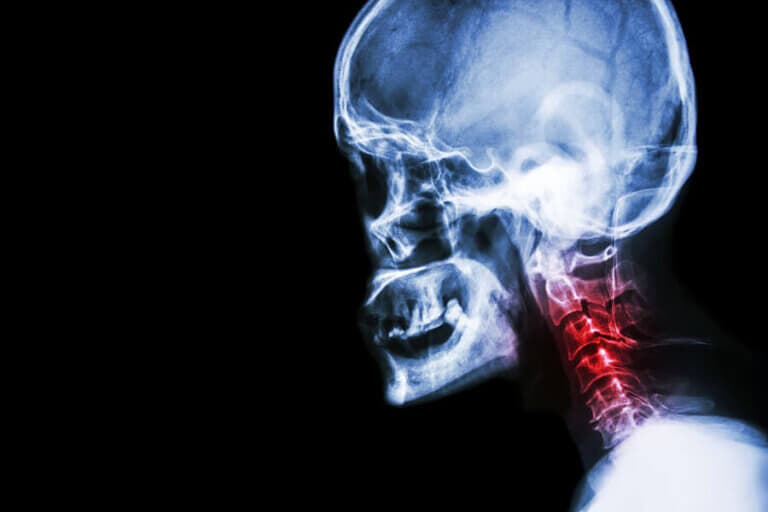

Una de las causas de dolor de cuello es la espondilosis cervical. Se trata de un trastorno en el que hay un desgaste de dos elementos de la columna vertebral en concreto: el cartílago y los huesos del cuello.

De acuerdo con el Dr. Rubin, “la espondilosis cervical es una degeneración de los huesos del cuello (vértebras) y de los discos intervertebrales, lo que ejerce presión sobre la médula espinal (la comprime) en la zona del cuello”. De allí que resulte una afección tan dolorosa.

Cabe destacar que la intensidad de los síntomas no siempre se correlaciona con lo que se aprecia en los estudios por imágenes. De hecho, existen muchos pacientes de más de 60 años de edad que no tienen síntomas y en los que los signos radiológicos son un hallazgo.